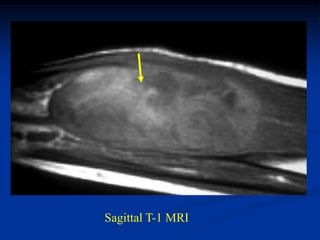

Case #1170.1              P.O. desmoid

61 year female with OA knee in 3/06 prior to TKA

Sag MRI 4/03

T-1                  T-2